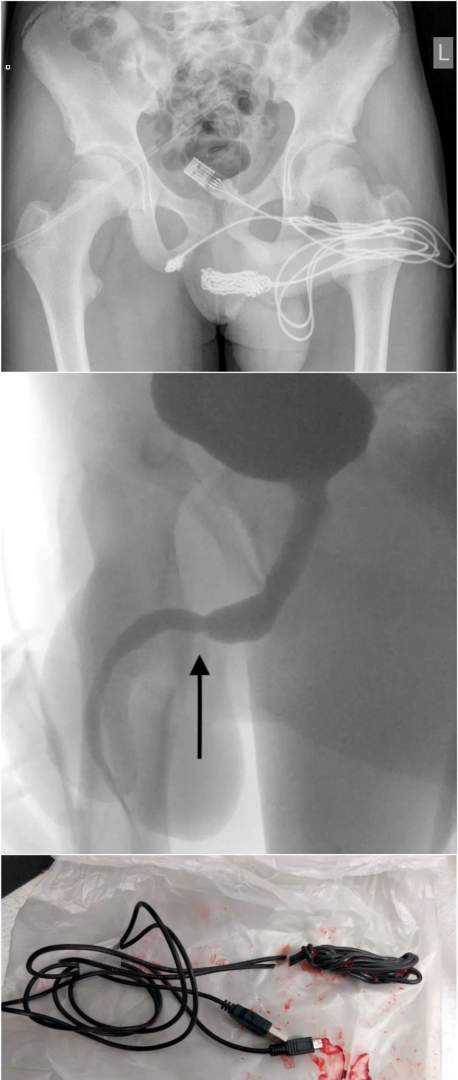

英国少年疫情期间在家闲着无聊,

拿usb线插入不该插的地方,

结果usb线在里面打结了,

搞得医生对差点取不出来。